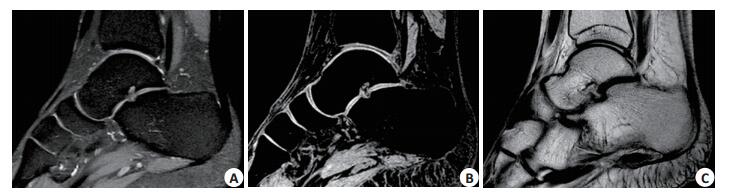

3种序列分别评估踝关节胫距、胫跟、胫舟软骨的成像质量,各数据间均有统计学差异(P < 0.05,表 5),3D-FFE的软骨成像质量最好,其次为3D-FSE,最后为2D-FSE(图 1)。

图 1 软骨的显示 Figure 1 MR scan of the ankle cartilage using 3D-FSE (A), 3D-FFE (B), and 2D-FSE (C) sequences. A: The cartilage outline appears obscure but the cartilage and subchondral bone interface was clear; B: The cartilage outline is shown clearly with sharp contrast between the cartilage and subchondral bone C: The cartilage outline and interfaces between the cartilage and the surrounding tissues are not clear. |